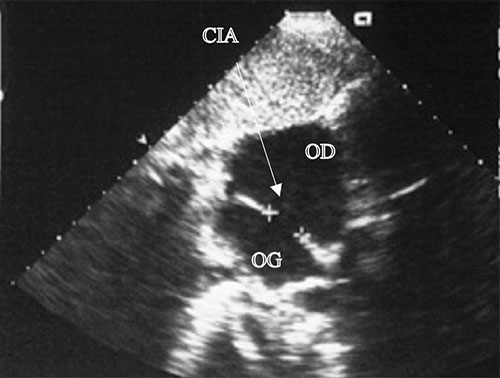

Fig. 11.8 ![]() Large communication interatriale (CIA) : échocardiographie transœsophagiennee (ETO).

Large communication interatriale (CIA) : échocardiographie transœsophagiennee (ETO).

Les CIA de l’adulte, mêmes larges comme celle-ci qui mesure 23 mm de diamètre, sont souvent mal visibles en ETT et nécessitent souvent pour leur visualisation le recours à l’échographie transthoracique (ETO). De surcroît, l’ETO est indispensable pour préciser la topographie et le diamètre exacts de la CIA, afin de déterminer si une fermeture par ombrelle percutanée est possible, ou s’il faut recourir à la chirurgie. OD : oreillette droite ; OG : oreillette gauche.